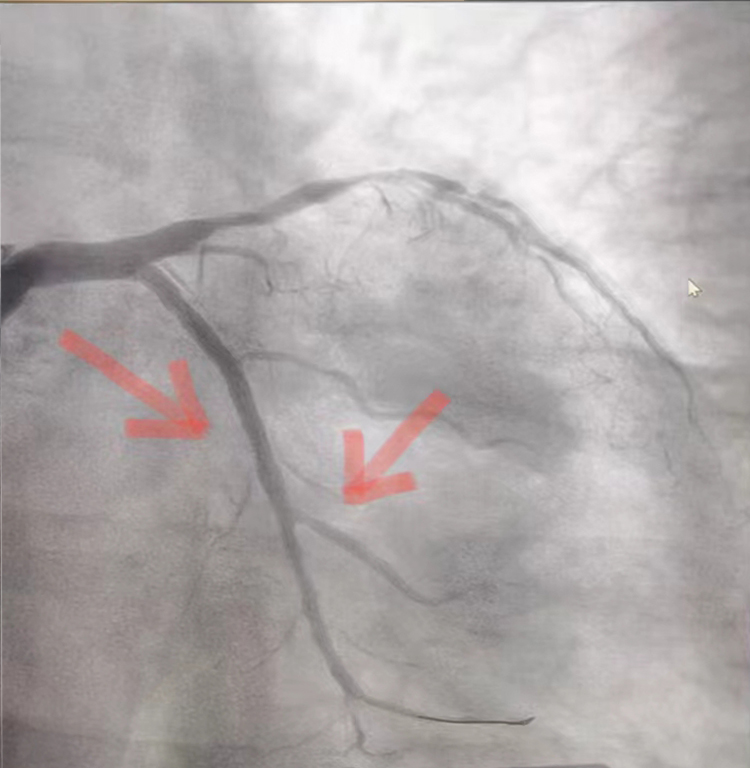

术前

术后

无独有偶,术后短暂休息时刻,又一位64岁突发急性心梗并心衰患者转入CCU,考虑到患者病情较重,副主任李雷再次投入战斗。在第一时间给予抗血小板、抗凝治疗的同时和家属沟通病情,联系导管室及我院介入团队邢建龙医生急行冠脉造影,显示患者冠脉三支重度病变,左冠弥漫性钙化,回旋支自近段100%急性闭塞,前降支近段80-90%狭窄,自中段100%慢性闭塞。病情危重,情况紧急!患者回旋支及前降支有急诊PCI指征,但术中可能出现恶性心律失常、低血压休克,甚至猝死可能,李主任再次和家属沟通病情,征得家属同意后签署相关知情同意书。事不宜迟!抢救仪器及药品就绪,立即追加肝素,沿桡动脉鞘管送EBU3.5指引导管至左冠开口,手术开始。9分钟后,导丝顺利通过旋支狭窄部位并应用硬球囊预扩完成,造影提示病变血管再灌注,借助支架精准定位技术,成功将一枚2.75×16mm支架植入旋支近段。球囊后扩后复查造影示支架展开良好。然而手术医生不敢有丝毫懈怠,继续乘胜追击,终将导丝通过前降支慢性病变并对其成功实施冠脉成形术,再次造影示冠脉无夹层、撕裂,前向血流通畅。29分钟后患者安返病房,后胸痛及憋喘症状逐渐缓解,心电图示心肌缺血明显改善。目前病人恢复良好,预计不久即可出院。